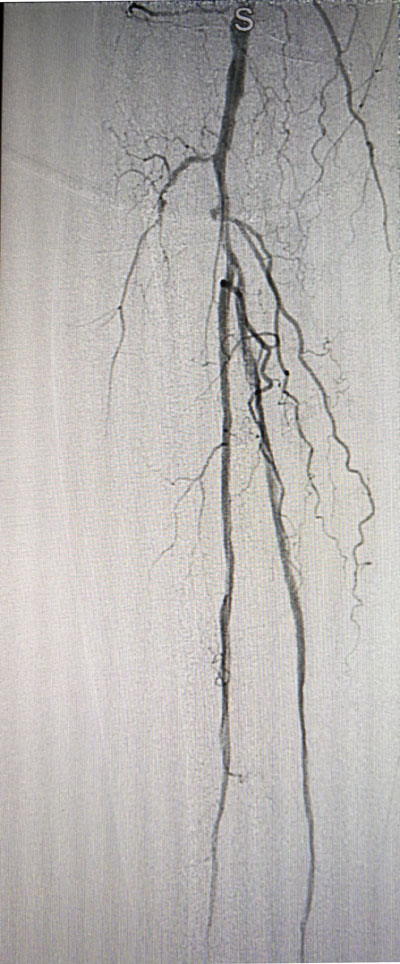

放射科导管室内做好了术前准备,患者由无创呼吸机及各种循环支持下开始介入手术,术中重症监护科严密观察患者的生命体征,内分泌科医生负责手术,患者下肢血流极差,膝下仅存一条多处严重狭窄的腓动脉供血,主要供血的胫前动脉及胫后动脉均长段闭塞,顺行穿刺成功后导丝下行困难,故采用踝下胫后动脉逆穿对接技术成功通过病变。经过近5个小时的奋斗,手术顺利完成,患者腓动脉及胫后动脉血流通畅,血流直达足底动脉环,患者感到足部逐渐温暖,术后清创时患者创面血流丰富。

治疗前